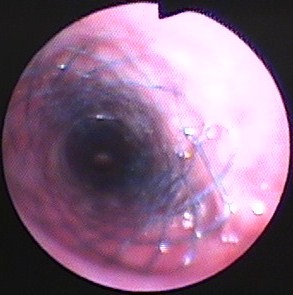

図5 気道ステント内部の気管支鏡所見。気管内部にフィットしている。気管支鏡ではステント端部の肉芽形成、内部の細菌感染、粘液停滞の程度を観察する。